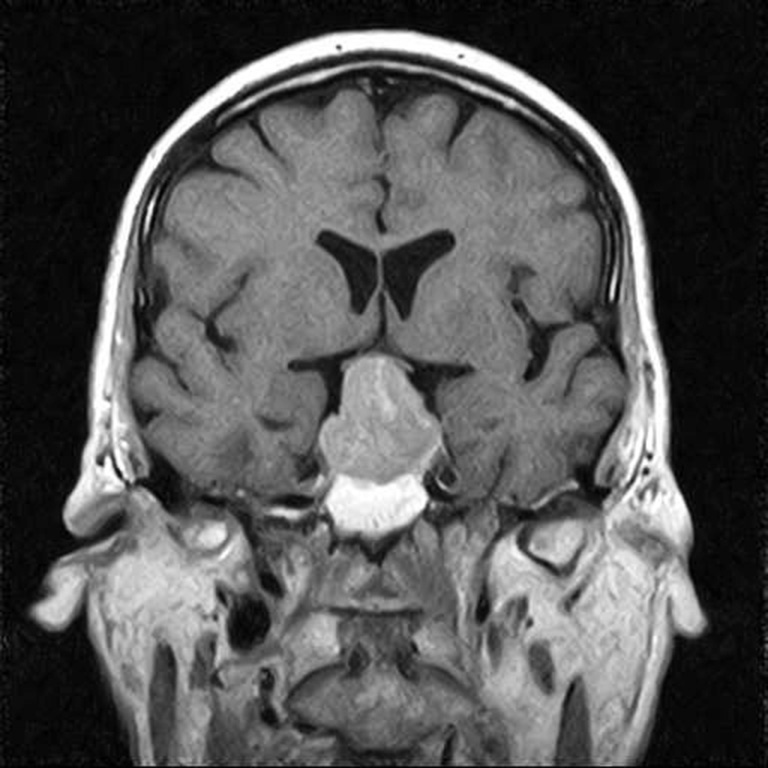

A B

Fig. 3. Patient B., 58 years old, HIPA with retrosellar extension, anterior chiasmal position. Brain MRI: A – sagittal projection; B – coronal projection